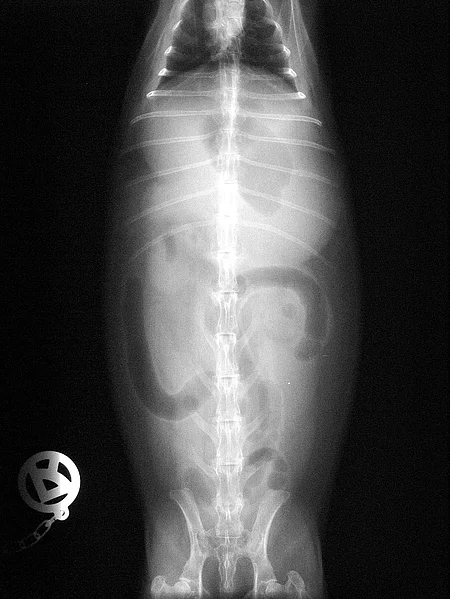

Sowohl Röntgenaufnahmen als auch eine Ultraschalluntersuchung bedeuten weiteren Stress für den Notfallpatienten. Daher muss stets abgewogen werden, welche Informationen unmittelbar nach Erstversorgung und Stabilisierung des Patienten benötigt werden oder welche Untersuchung ggf. auf den Folgetag geschoben werden kann. Kurzfristig notwendig sind Röntgenaufnahmen vor allem bei Verdacht auf Frakturen, zur Verifizierung und Beurteilung einer Magendilatation oder zur Darstellung der Lunge.

Besteht der Verdacht auf eine Verletzung der Wirbelsäule oder des Rückenmarks, so muss auf das ansonsten übliche vollständige Durchstrecken der Wirbelsäule beim Röntgen zunächst verzichtet werden.